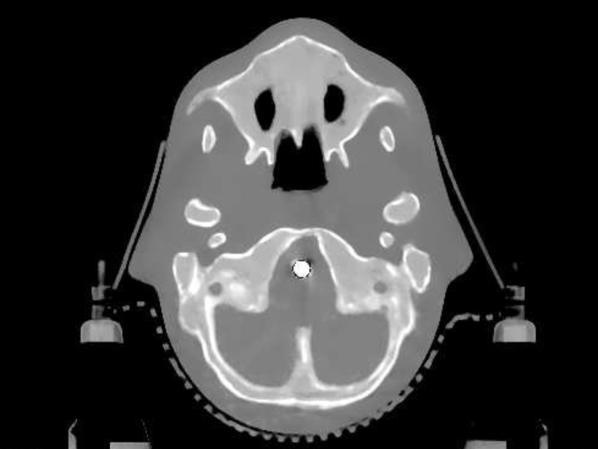

The data we used for our numerical reconstruction test were derived from the Adult Reference Computational Phantom (ICRP Publication 110,, 2009), which is a segmented image of defined density and chemical composition to represent real tissues. To investigate the ability to image metal implants, we inserted a pair of prosthetic hip joints (marked in green) with a solid titanium pin and shell. The slices through the chest and pelvis—which are the images we selected for testing—are shown in Figure 8. The resolution is 299×137299137299\times 137.

Refer to caption

(a) Chest test image

(b) Pelvis test image

Figure 8: Experimental data used: (a) is the oracle chest electron density; and (b) is the oracle pelvis electron density; both have a with display window of [0.8,1.2]